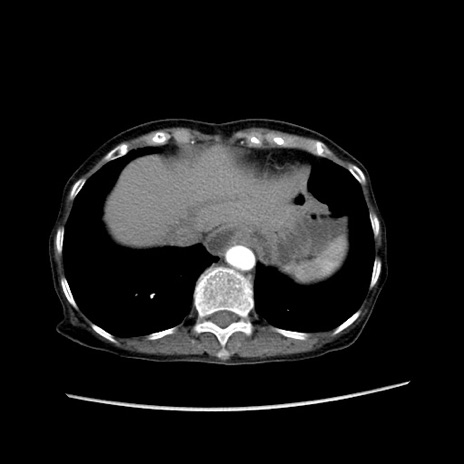

症例25(横断像)

【症例】80歳代女性

【主訴】胸のつかえ感

【現病歴】約9時間前に食後から胸のつかえた感じあり、嘔吐あり、来院。

【既往歴】胃癌(全摘)、胆摘、虫垂炎

【身体所見】心窩部に圧痛あり、反跳痛なし。

【データ】WBC 5700、CRP 0.05